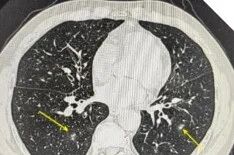

更让人意外的是,张大爷并不是我们通常认为容易感染这种病菌的免疫力低下患者,他的身体状况相对良好,免疫功能正常,却感染了这种素有“致命杀手”之称的真菌。那么什么是马尔尼菲篮状菌病?这种真菌感染的症状往往很隐蔽,患者多表现为咳嗽、咳痰、胸痛,很容易被当作普通的肺炎或咽喉炎来处理。肺部影像学也缺乏特征性改变,多类似于肺炎、肺结核或肺脓肿病变。正是因为这些症状、检查缺乏特异性,很多患者像张大爷一样,在确诊前经历了漫长的求医过程。如何预防和应对?诊断有一定难度可完全治愈如果您在竹林附近居住或工作,可能接触过竹鼠等野生动物,或在流行地区居住或旅行,那么您就属于这种疾病的高危人群。